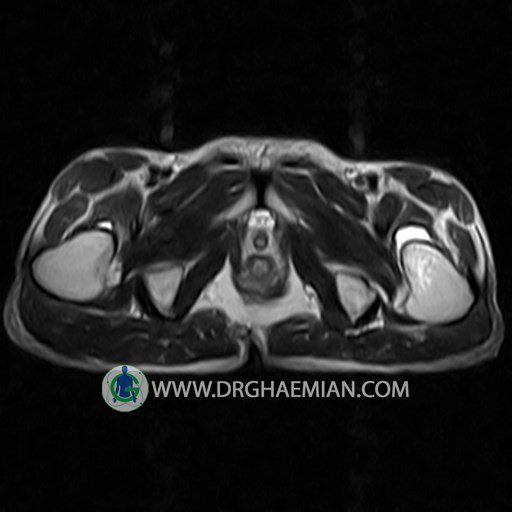

پزشکان اغلب از تصویربرداری ام آر آی برای تشخیص و درمان عارضه های پزشکی که فقط با استفاده از اشعه ایکس یا میدان مغناطیسی و امواج رادیویی قابل مشاهده است، استفاده می کنند. دستگاه ام آر آی تصاویر دقیق از ساختار های داخلی بدن ایجاد می کند. در این کیس استئومیلیت لگن، آتروز و سنیویت دیده می شود.

HIP JOINT MRI

( without contrast )

Technique : coronal STIR , coronal T2 , Axial T1 , axial T2 .

REPORT:

– Heterogeneous signal change (high T2/STIR , low T1) in proximal metaepiphysis of left femur without articular surface irregularity suggestive for bone bruise (stress fracture?), osteomyelitis & arthritis and marrow infiltration (less probable)

– Left hip joint effusion suggestive for synovitis

are seen.

COMMENT: Clinical correlation and MRI with contrast are recommended.